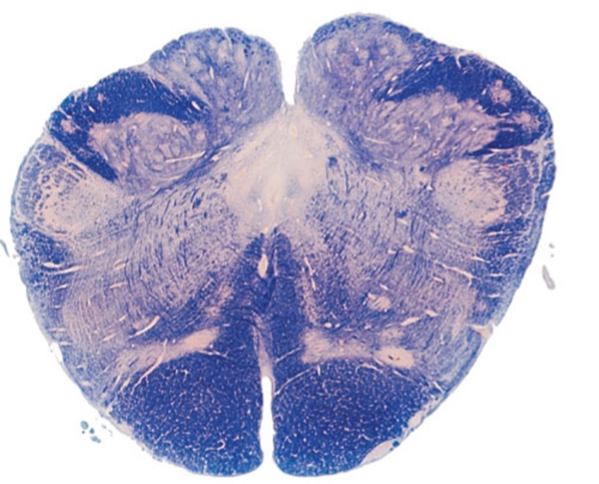

7

The highlighted structure is?

A

middle cerebellar peduncle

11

The outlines structure is?

substantia nigra